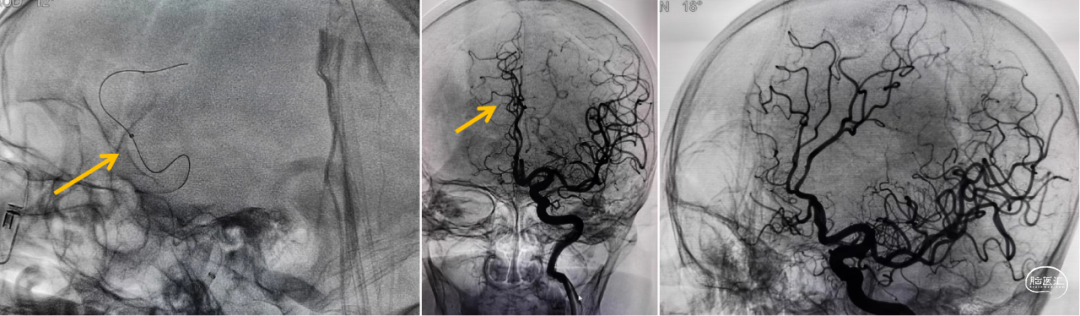

微导丝+微导管velocity辅助血栓抽吸导管4MAX到达右侧大脑前动脉A2段抽吸,抽吸1次后造影右侧大脑前动脉血流恢复,但左侧大脑前动脉仍闭塞。

微导丝+微导管velocity辅助血栓抽吸导管4MAX超选到达左侧大脑前动脉A3段抽吸,抽吸1次后造影左侧大脑前动脉部分再通、A3段远端仍有栓塞。

微导丝辅助微导管velocity到达左侧大脑前动脉A3段以远抽吸,利用微导管velocity持续抽吸后造影左侧大脑前动脉完全再通、前向血流Ⅲ级;最终双侧大脑前动脉血流恢复、前向血流Ⅲ级;左侧大脑中动脉下干远端栓塞部位血管细小迂曲故未干预、手术结束。